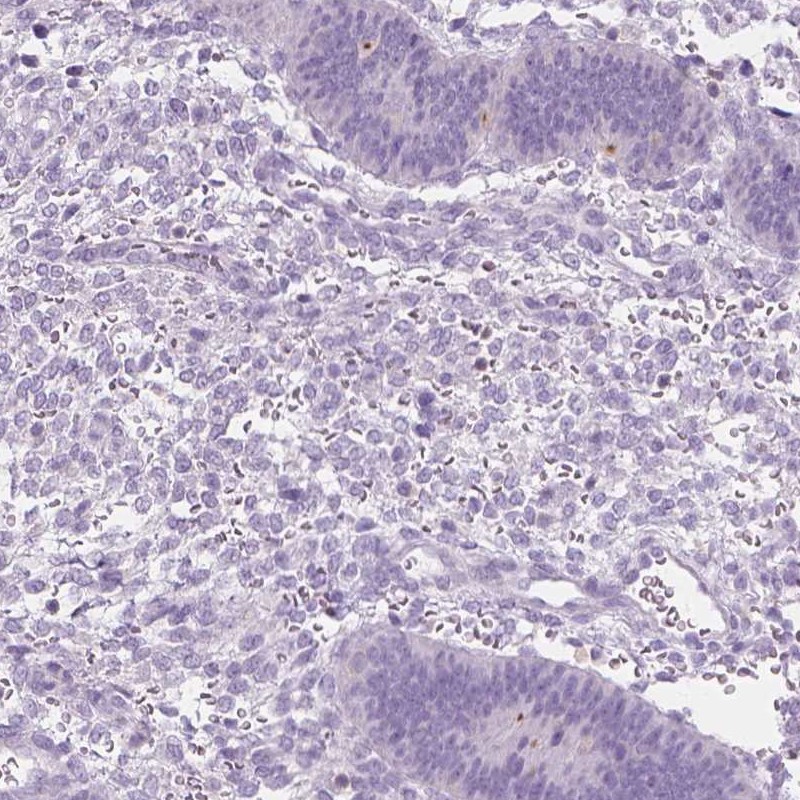

Immunohistochemistry analysis in human testis and endometrium tissues using Anti-DCAF8L1 antibody. Corresponding DCAF8L1 RNA-seq data are presented for the same tissues.